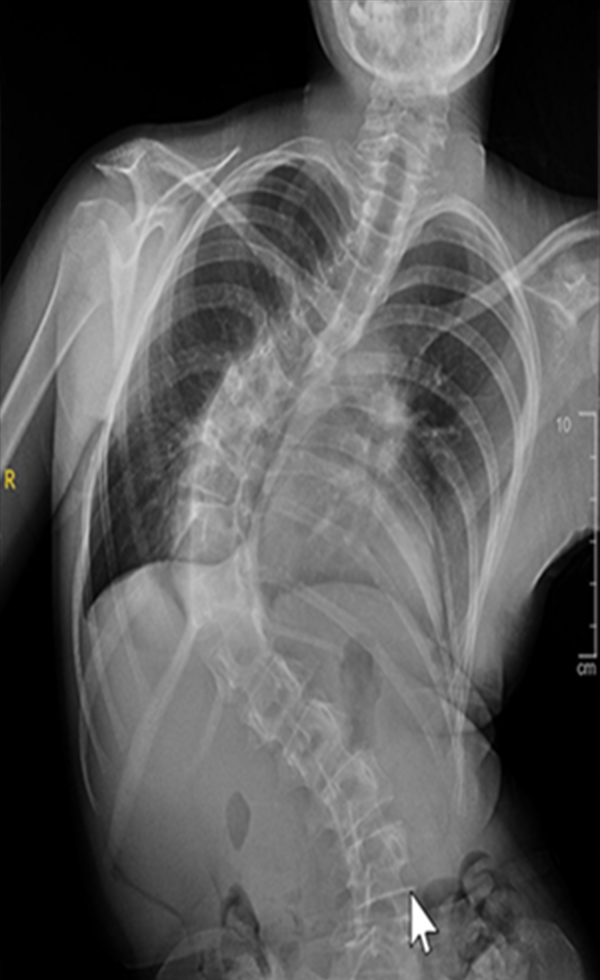

Gallery : Before - After